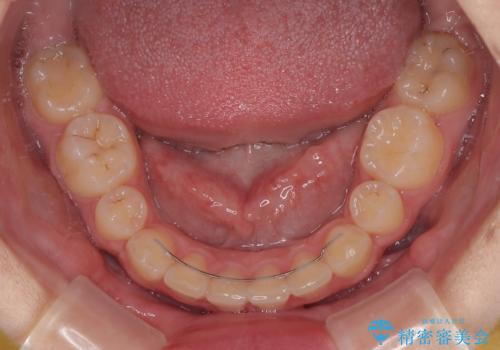

- 下唇の上に乗っかってしまうくらい前歯が飛び出していることを気にして来院された患者様です。

唇を閉じようとするとオトガイ部に力が入ってしまい、うまく閉じることができない状態であったため、上下左右の第一小臼歯4本を抜歯して、ワイヤー装置にて矯正治療を行うこととしました。

飛び出した前歯はしっかりと引っ込み、横顔の印象が大きく変化しました。